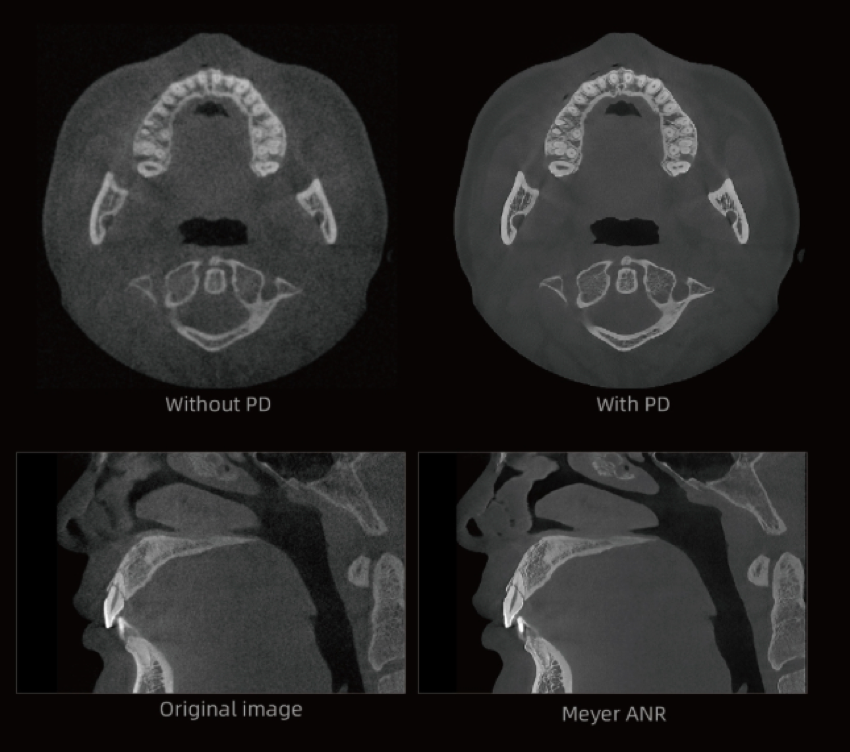

Algoritmo PD-MAR de Redução de Artefactos Metálicos

Tecnologia de correcção de artefactos líder na indústria, que elimina eficazmente artefactos persistentes em todos os cenários clínicos.

Restaura com precisão os detalhes estruturais dos tecidos.

Suporta Utilização Imediata e Comparação com Um Clique, melhorando significativamente a eficiência diagnóstica.

Elimina a necessidade de guias radiográficas, permitindo que as imagens processadas sejam utilizadas directamente na fabricação de guias cirúrgicas digitais para implantes.